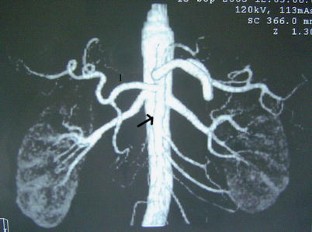

A variation in liver vascularization was discovered in a 50-year-old man. A single common hepatic artery was found to be responsible for vascularization of the entire liver. This artery was unusual in that it formed the first branch of the superior mesenteric artery, crossing the portal trunk shortly after its origin, and passed in front of the portal vein to reach the hilum of the liver, where it divided into a right and a left branch. This artery was a true common hepatic artery because a gastroduodenal artery emerged from it 2 cm after its origin. A common hepatic artery originating from the mesenteric artery and passing in front of the portal vein has never been described before. The patient had a second anatomical variation: the left gastric artery and the splenic artery arose directly from the aorta, without celiac trunk separation. This observation confirms the importance of carrying out a precise vascular assessment before all types of hepatic or pancreatic surgery, to identify possible variations in the number or trajectory of hepatic arteries.

Fig. 4